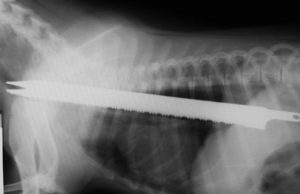

The Complete Guide on Osteosarcoma in Dogs

Each year approximately 8,000 to 10,000 dogs are diagnosed with osteosarcoma. Most frequently seen in large and giant breed dogs, this aggressive bone cancer...